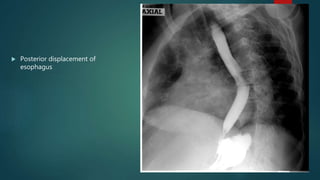

 Posterior displacement of

esophagus

• #10 LA is located just anterior to the mid part of thoracic oesopagus, Enlarges posteriorly. Barium Swallow